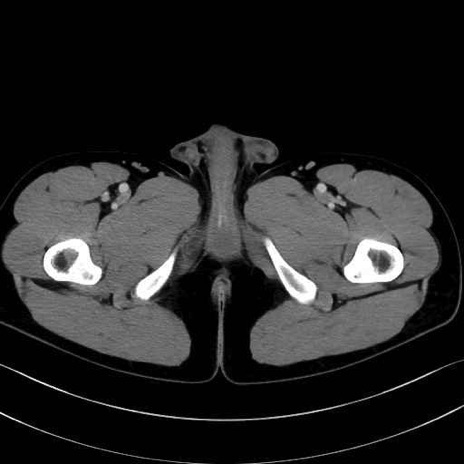

内閉鎖筋 (Obturator internus)

外閉鎖筋 (Obturator externus)

大腿方形筋 (Quadratus femoris)

縫工筋 (Sartorius)

恥骨筋 (Pectineus)